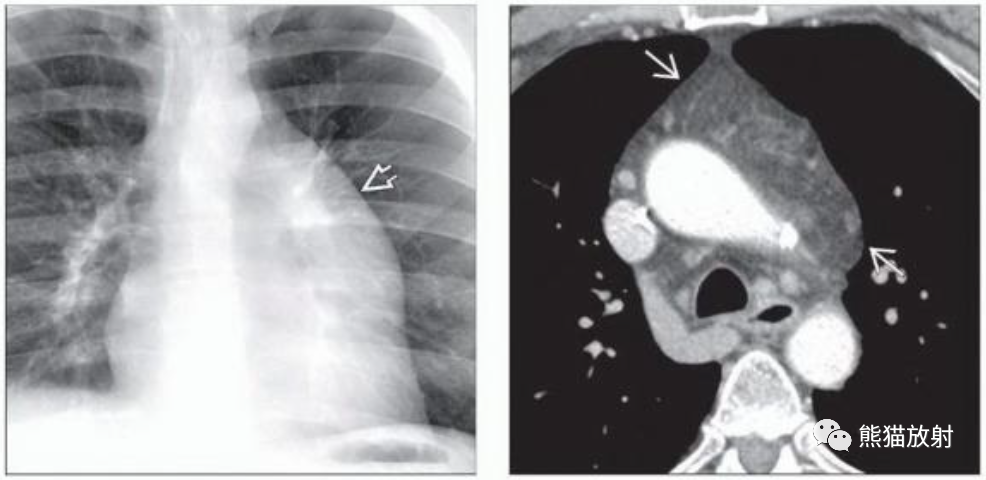

(左)17岁胸腺脂肪瘤患者,PA胸片显示左前纵隔肿块,显示肺门重叠征。胸腺脂肪瘤多见于年轻患者,无症状。

(右)胸腺脂肪瘤患者的轴位CECT显示左前纵隔肿块,位于胸腺解剖位置,脂肪密度为主,内见条状、结节状软组织密度。